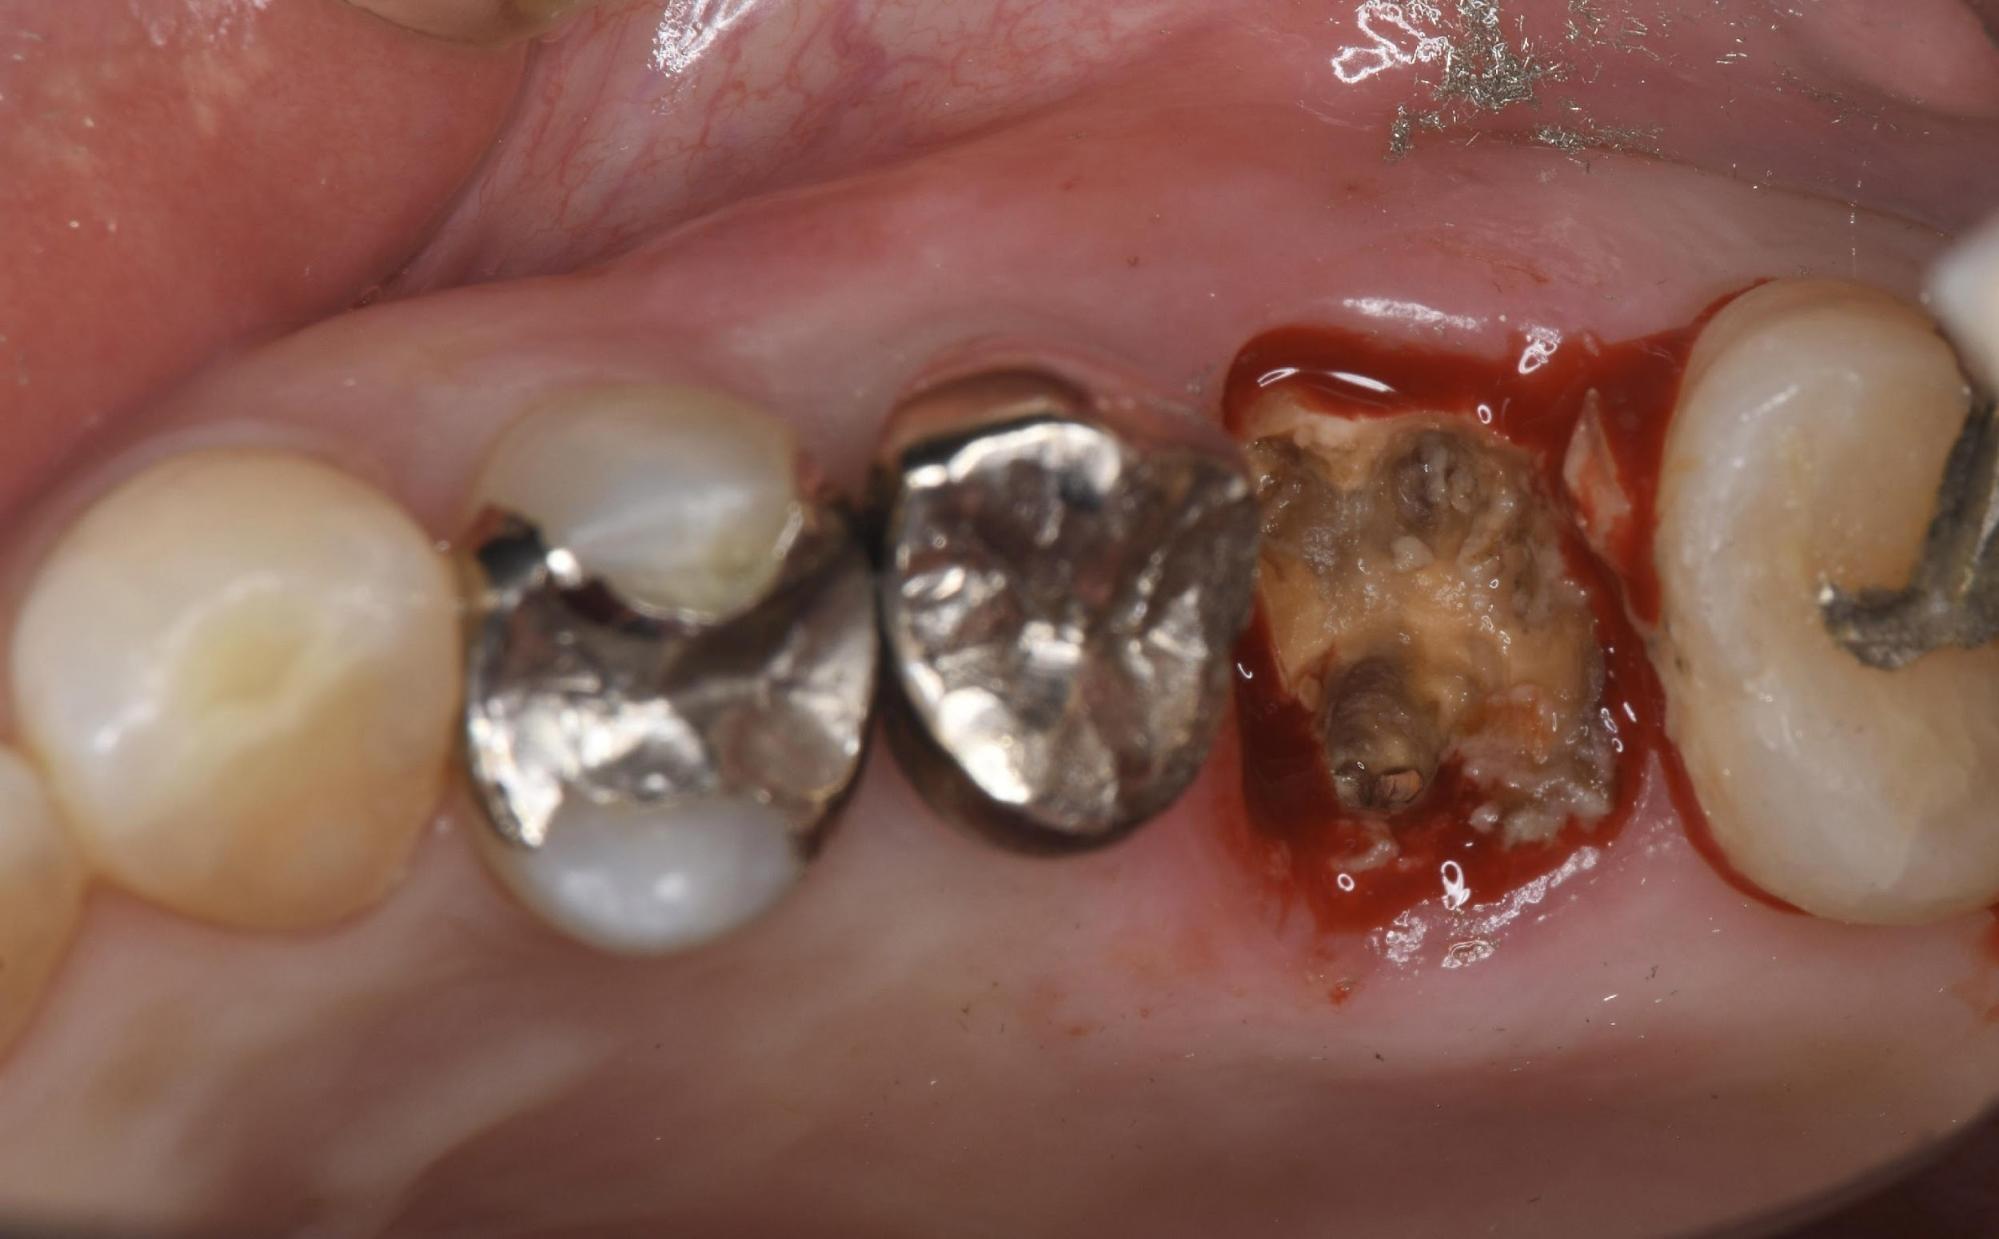

まずは問題となっている銀歯を外しました。すると、事前のCT診断で想定していた通り、内部のむし歯は重度に進行しており、歯質のほとんどが失われていました。

①丁寧な抜歯

周囲の骨を傷つけないよう、マイクロスコープ(歯科用顕微鏡)なども活用しながら、慎重かつ丁寧に歯を抜きました。インプラントを成功させるためには、この「周囲の骨を残すこと」がとても重要です。